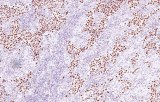

Primary antibodies for immunohistochemistry CE/IVD - Pediatric pathology

Perinatal/paediatric pathology is a medical subspecialty with particular expertise in diseases affecting the placenta, fetus, infant and child. Although many conditions that affect adults also affect children, pediatric pathology includes many conditions found only in patients younger than 18 years of age. One group of conditions involving the infant population is congenital anomalies. A malformation is a congenital anomaly due to an intrinsic defect in development. A disruption occurs when a normally developing organ is secondarily damaged by another process. A sequence is a collection of several anomalies, all of which are due to one malformation, disruption, or deformation. Finally, a syndrome is a group of related anomalies. An other group is the pediatric cancers or childhood cancers. Childhood cancers include many that also occur in adults. Leukemia is by far the most common, representing about 33% of childhood cancers, brain tumors represent about 25%, lymphomas represent about 8%, and certain bone cancers (osteosarcoma and Ewing sarcoma) represent about 4%.